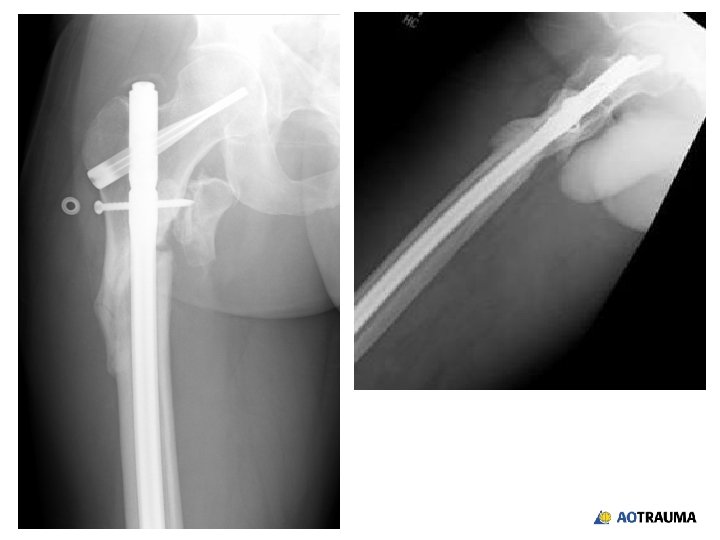

28 -year-old male, motor vehicle accident, subtrochanteric femoral fracture

Reduction? 1. Open direct reduction 2. Closed indirect reduction 3. Mini-open reduction

How would you achieve an indirect reduction? 1. Fracture table 2. Regular radiolucent table 3. Femoral distractor/external fixator 4. Implant as a reduction aid